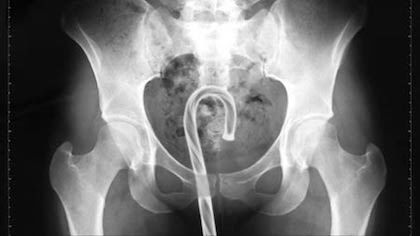

Further findings from rectums: A look back at what was in behinds

Barry Petchevsky performed his annual data-gathering exercise “What Did We Get Stuck In Our Rectums Last Year?” in Deadspin:

All reports are taken from the U.S. Consumer Product Safety Commission’s database of emergency room visits, and they are occasionally not for the faint of spirit….

Petchevsky’s prodigious mining operation is in the tradition of the medical study that won the 1995 Ig Nobel Literature Prize. That prize was awarded to surgeons David B. Busch and James R. Starling, of Madison Wisconsin, for their deeply penetrating research report, “Rectal foreign bodies: Case Reports and a Comprehensive Review of the World’s Literature,” published in the journal Surgery (September 1986, pp. 512-519).

The Busch/Starling compendium include reports of, among other items: seven light bulbs; a knife sharpener; two flashlights; a wire spring; a snuff box; an oil can with potato stopper; eleven different forms of fruits, vegetables and other foodstuffs; a jeweler’s saw; a frozen pig’s tail; a tin cup; a beer glass; and one patient’s remarkable ensemble collection consisting of spectacles, a suitcase key, a tobacco pouch and a magazine.

The Busch/Starling compendium contains multitudes. It bears repeat visits.